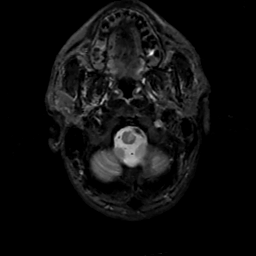

MR Study #14, June 2, 1991 -- Slice #3

[Home][Help][Clinical][Tour 1][Tour 2] Slice 3